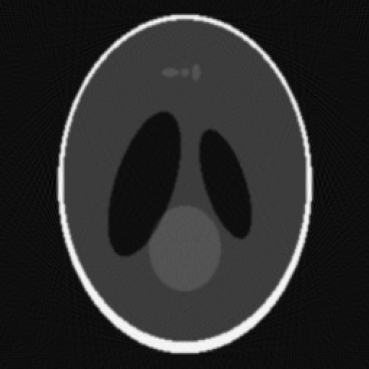

Figure 1: Visualization of simulated artifacts with Shepp Logan Phantom.

The framework now includes advanced tools for simulating realistic imaging artifacts. These include features such as detector jitter, Poisson noise, Gaussian noise, ring artifacts, and gantry motion blur. The ability to simulate such artifacts enables the training and validation of deep learning models under realistic imaging conditions, leading to more robust and generalizable reconstructions. These tools also allow researchers to explore the impact of different types of noise and artifacts on reconstruction quality in a controlled environment.